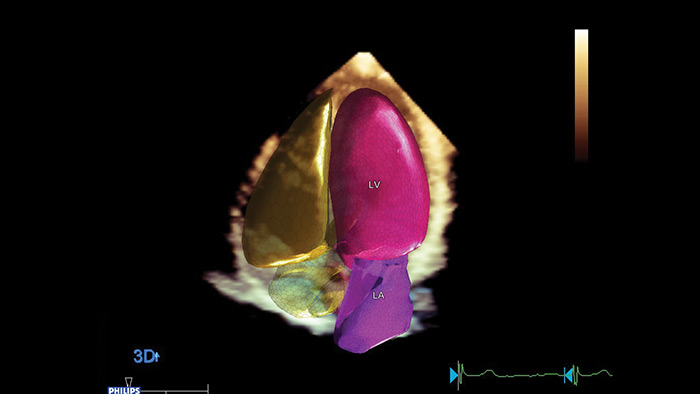

Kardiologische Quantifizierung für mehr Diagnosesicherheit Philips Dynamic HeartModelA.I. ist ein 3D-Tool, das die Ejektionsfraktion (EF) als Teil eines Routine-Arbeitsablaufs innerhalb von Sekunden zuverlässig und reproduzierbar misst.

Das Management des Kardiotoxizitätsrisikos setzt eine Zusammenarbeit zwischen Kardiologen und Onkologen voraus. Im Idealfall wird mit einer kardiologischen Voruntersuchung von Patienten begonnen, denen potentiell kardiotoxische Substanzen verabreicht werden sollen.4 Bei der einfachen und überaus gängigen Beurteilung der linksventrikulären Ejektionsfraktion (LVEF) mittels 2D-Echokardiographie werden jedoch oftmals kleine Veränderungen der linksventrikulären Kontraktilität nicht erkannt. Genauere Messungen bietet die 3DEF. Beide Analysen können jedoch durch den globalen longitudinalen Strain (GLS) ergänzt werden, den am besten geeigneten Deformationsparameter, der die frühzeitige Erkennung einer subklinischen LV-Dysfunktion zulässt.4